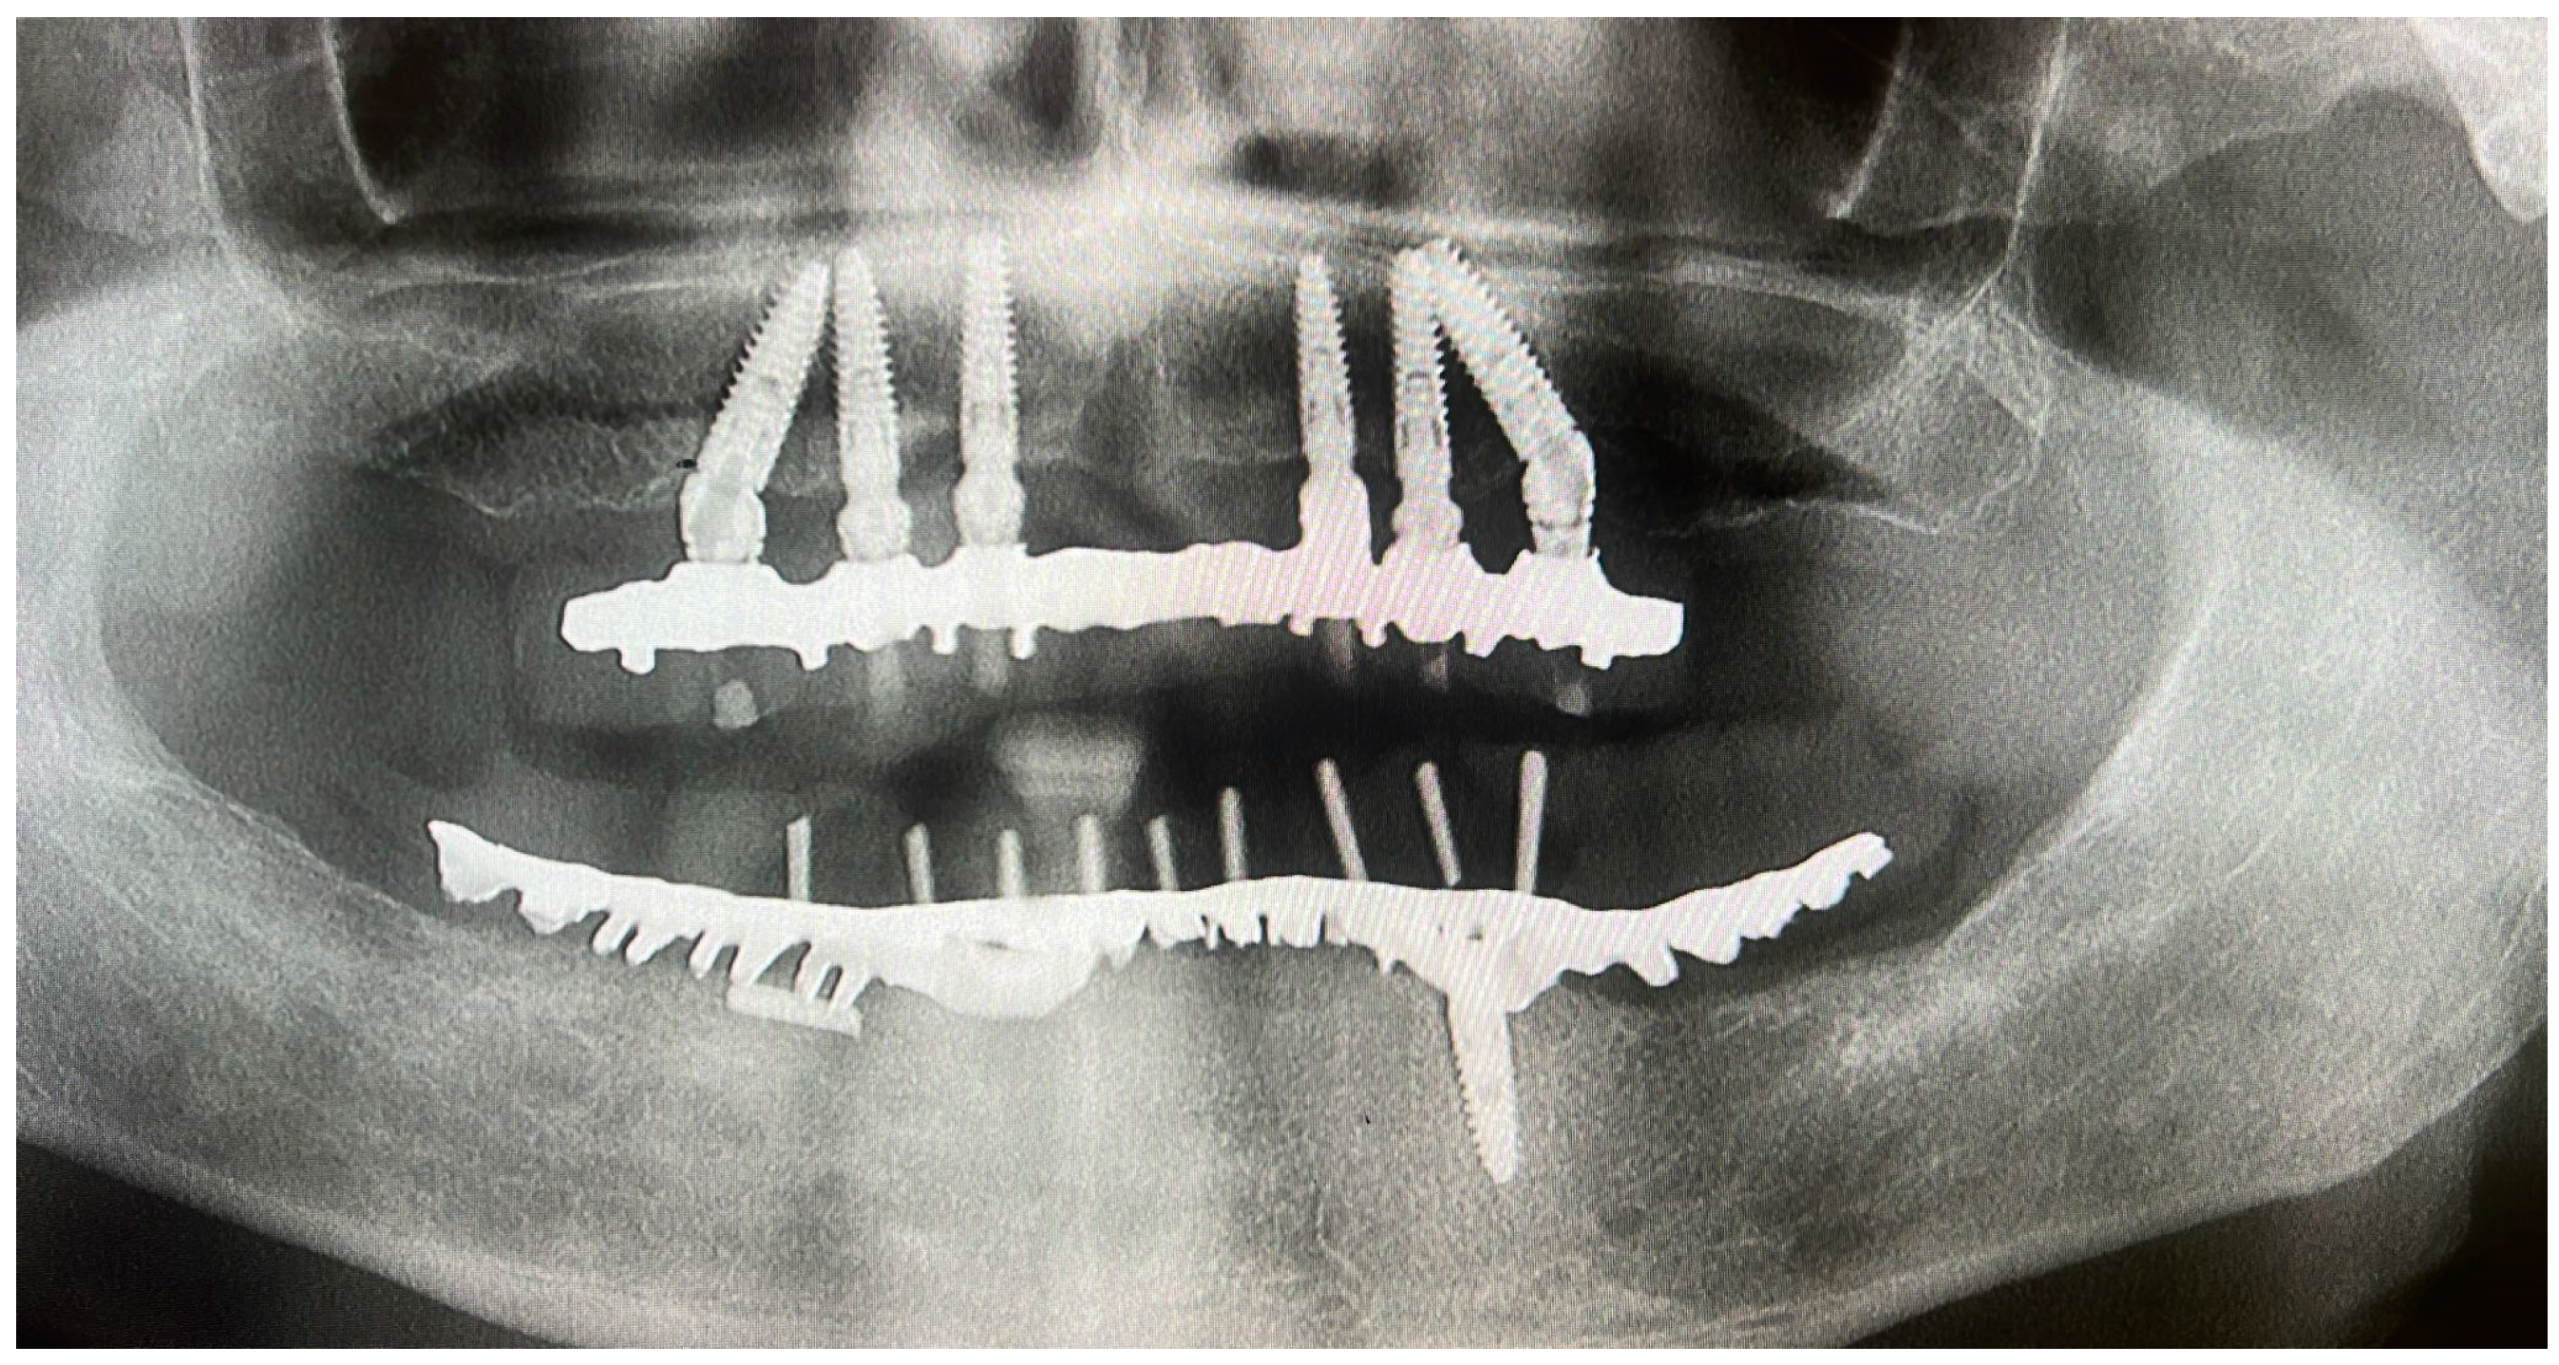

3. Case Presentation